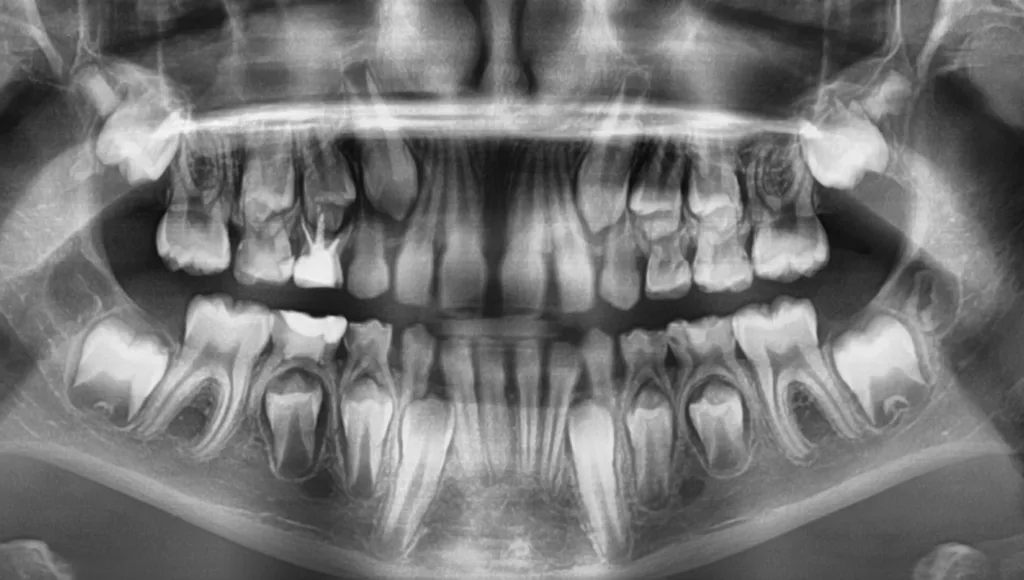

Unter Lokalanästhesie mit dem STA-System (Milestone Scientific, USA) und Septanest 1/200 000 (Septodont, Frankreich) wurde die überstehende Gingiva mit dem Khors Koagulator (Эctatex, Ukraine) koaguliert und der Bereich unter Kofferdam kontaminationsfrei dargestellt (Klammer U67, KSK Dentech, Japan). Die schmalen Fissuren wurden mit dem Fissurenbohrer CD-53F (Mani, Japan) erweitert, um anschließend mittels RONDOflex plus 360 (KaVo Dental, Deutschland) und Pulver 27 µm vollständig gereinigt werden zu können. Es konnte weder durch visuelle Inspektion noch Sondierung mit 0.08 H-file (Mani, Japan) ein Defekt des Zahnschmelzes festgestellt werden. Unter Berücksichtigung der Integrität des Zahnschmelzes, der Symptomlosigkeit, des Behandlungszeitpunktes, Alters des Kindes und Wachstums der Zahnwurzeln fiel gemeinsam mit den Eltern die Wahl auf eine konservative Therapie. Es wurde eine Fissurenversiegelung mit Clinpro Sealant (3M, USA) unter Anwendung eines adhäsiven Behandlungsprotokolls mit Optibond FL (Kerr, USA) durchgeführt. Dieser klinische Fall ist dahingehend einzigartig, da alle anderen ersten und zweiten Molaren des Kindes ebenso von einer PEIR betroffen waren (Grad 1 bis 2 der Läsion nach Seow) (Abb. 3 und 12). Normallerweise ist nur ein Zahn bei einer Patientin oder einem Patienten betroffen. Die Zahnkronen der anderen betroffenen Zähne erwiesen sich bei der klinischen Untersuchung als intakt; die radioluzenten Läsionen innerhalb des koronalen Dentingewebes waren wesentlich kleiner als die von Zahn 36. Daher wurde auch bei diesen Molaren das gleiche Behandlungsprotokoll angewendet und nur eine Fissurenversiegelung durchgeführt.

Das 13-jährige Mädchen wurde von unserer Kollegin mit der Bitte um die Behandlung des in der Durchbruchsphase befindlichen, symptomfreien Zahnes 37 an uns überwiesen. Es zeigte sich eine umfangreiche Resorption von Zahnschmelz und Dentin fast bis zum Pulpakavum (Grad 3 der Läsion nach Seow), die voll mit Weichgewebe gefüllt war (Abb. 29 und 30). Auf einer Panoramaschichtaufnahme, die vor zwei Jahren während der kieferorthopädischen Anfangsuntersuchung angefertigt wurde, wies der Zahn 37 keinerlei Anzeichen von PEIR auf (Abb. 31). Die Progredienz und der Umfang der Resorption in diesem Fall zeigen uns, wie aggressiv eine PEIR sein kann. Für die zuweisende Kollegin war es sehr schwierig, das resorbierende Weichgewebe zu entfernen, eine Diagnostik des Zustandes der Pulpa vorzunehmen und die Krone zu restaurieren. Deswegen kam die junge Patientin mit einer temporären Füllung aus Glasionomerzement zu uns (Abb. 32 und 33). Trotz der klinischen Symptomlosigkeit und fehlender radiologischer Befunde, die auf periapikale Veränderungen hinweisen, konnte aus der Ausdehnung der PEIR geschlussfolgert werden, dass die Pulpa bereits betroffen sein dürfte. Eine deutlich erschwerte Zugänglichkeit zum Zahn und die ausgeprägte Kurvatur der noch wachsenden Wurzeln ließen die übliche Wurzelkanalbehandlung problematisch erscheinen. Die verschiedenen Behandlungsmöglichkeiten von Vitalerhaltung der Zahnpulpa bis zur Extraktion wurden mit den Eltern des jungen Mädchens besprochen. Eine Extraktion des Zahnes hätte die Einordnung des Weisheitszahnes (entsprechend der kieferorthopädischen Konsultation) problemlos ermöglicht und somit auch die Kaufunktion vollumfänglich ohne eine verkürzte Zahnreihe sichergestellt. Trotzdem wollten die Eltern den Zahn 37 so lange wie möglich erhalten, auch um eine eventuelle Sedierung des Kindes während der Extraktion zu vermeiden.

Der elfjährige Junge stellte sich aufgrund von Schmerzen beim Essen im rechten Unterkiefer vor. Der intakte Milchzahn 85 exfolierte physiologisch vor einen Monat, der Zahn 45 war im Durchbruch. Sensibilitätstest, Perkussion und Palpation waren unauffällig. In der medialen Fissur war ein dunkler kleiner Zugang zur Läsion sichtbar und mit der Sonde detektierbar (Abb. 52). Das Ausgangsröntgenbild zeigte am Zahn 45 eine unförmige transluzente Zone, angrenzend an die mesiookklusale und -approximale Schmelz-Dentin-Grenze (Abb. 53). Auf einer zwei Jahre zuvor angefertigten Panoramaschichtaufnahme des Patienten im Rahmen der kieferorthopädischen Untersuchung in unserer Praxis war kein deutlicher Dentindefekt des Zahnes 45 erkennbar (Abb. 54). Ähnlich wie in Fall 4 wurde auch dieser PEIR-Defekt (Grad 2 der Läsion nach Seow) mit Komposit restauriert. Nach Infiltrationsanästhesie wurde unter relativer Trockenlegung mit Split-Kofferdam die PEIR-Läsion eröffnet (Abb. 55). Das intrakoronale Weichgewebe war blass und bereits nekrotisiert (Abb. 55). Die unförmige PEIR-Läsion wurde mit RONDOflex plus 360 (KaVo Dental, Deutschland) mit dem 27-µm-Pulver gereinigt, um nicht weiteres intaktes Dentin zu entfernen und alle versteckten Teile des PEIR-Defekts zu erreichen. Unter anderem wurde die PEIR-Läsion mit 5,25%igem NaOCl gespült, das in der Lage ist, zusätzlich zur antibakteriellen Wirkung mögliches residuales Weichgewebe aufzulösen (Abb. 56). Anschließend wurde die Läsion entsprechend der Vorgehensweise wie im zuvor beschriebenen klinischen Fall mit Komposit restauriert (Abb. 57). Die final angefertigte Röntgenkontrollaufnahme zeigte eine perfekte und vollständige Abdichtung der Läsion (Abb. 58). Nach 3 Monaten war der Junge beschwerdefrei und der Zahn zeigte weiteres Wachstum mit positiven Sensibilitätstest (Abb. 59 und 60).